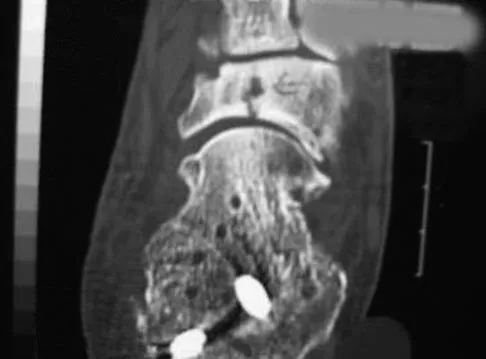

An 8-year-old boy with severe hemophilia A (factor VIII) and no inhibitor is averaging eight transfusions per month for bleeding into the right ankle. Examination shows synovial hypertrophy; range of motion consists of 0 degrees of dorsiflexion and 20 degrees of plantar flexion. The patient's knees, elbows, and left ankle have no restriction of motion. Standing radiographs of the right ankle are shown in Figure 18. Management should consist of

Explanation